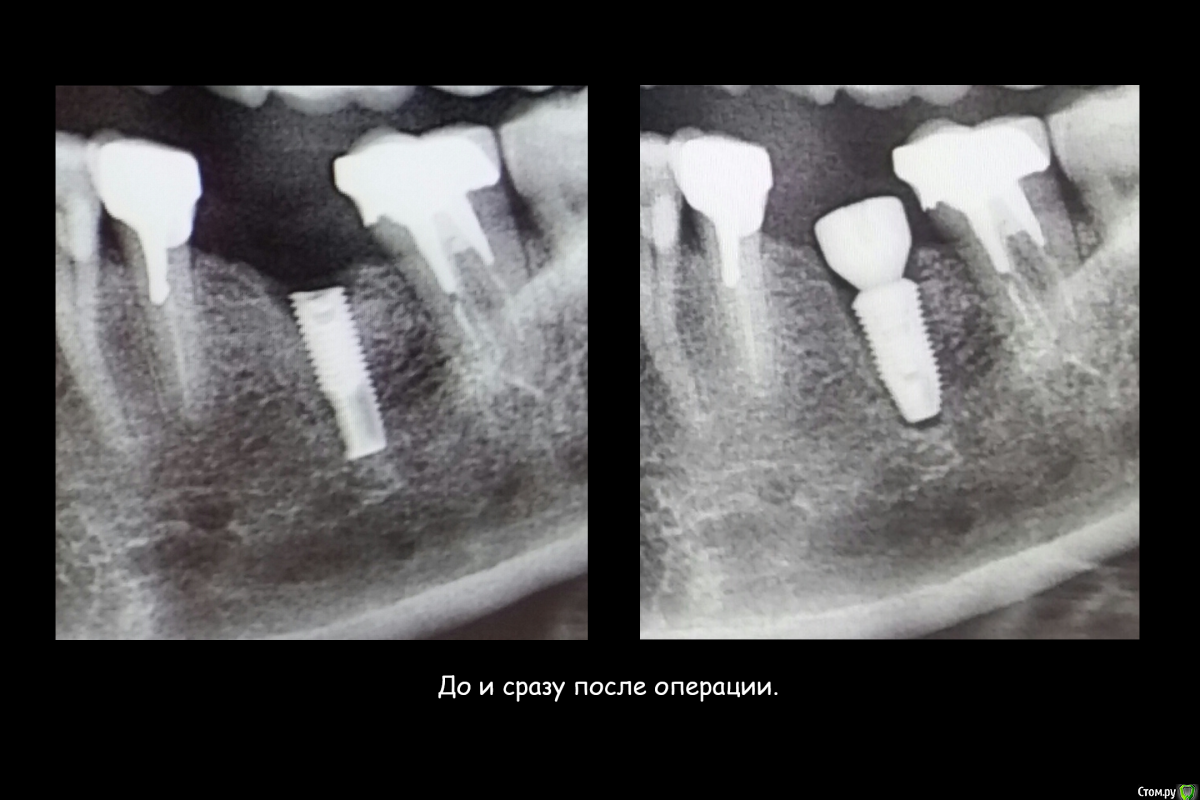

Этот имплантат, можно было лечить!!!!!!